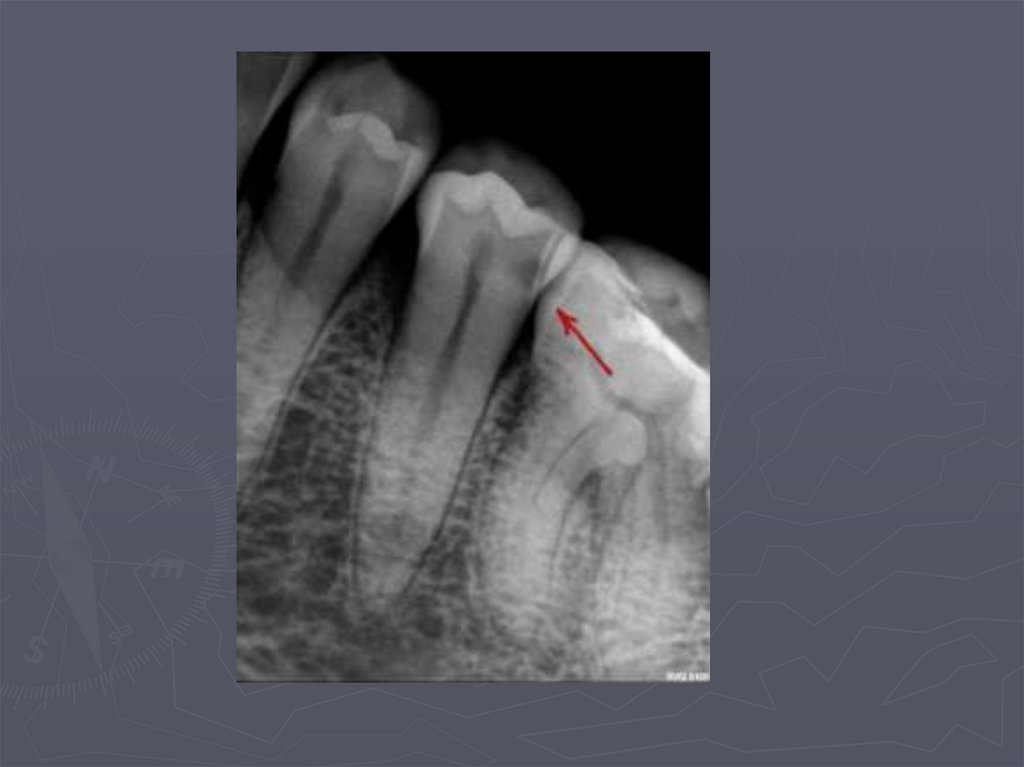

92. МЕТОДЫ ДИАГНОСТИКИ КАРИЕСА У ДЕТЕЙ

РЕНТГЕНОЛОГИЧЕСКИЙ МЕТОД –

применяется:

в случаях крайнего затруднения

диагностики,

► при локализации полостей на

апроксимальных поверхностях,

► при тесном положении зубов.

93. Кариес на рентгеновских снимках

94. Рентгенологическая классификация кариеса

95. МЕТОДЫ ДИАГНОСТИКИ КАРИЕСА У ДЕТЕЙ